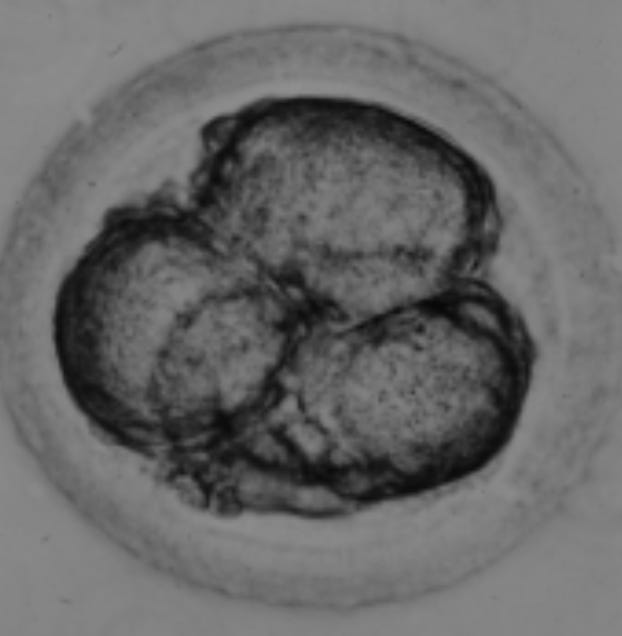

Figure 1. demonstrates an egg shortly after being fertilized by ICSI. Quite often, the egg contracts away from the zona pellucida, a sign that forces are being generated in the cytoplasm that will rearrange the various organelles so that they are equally distributed each time the embryo divides by mitosis.